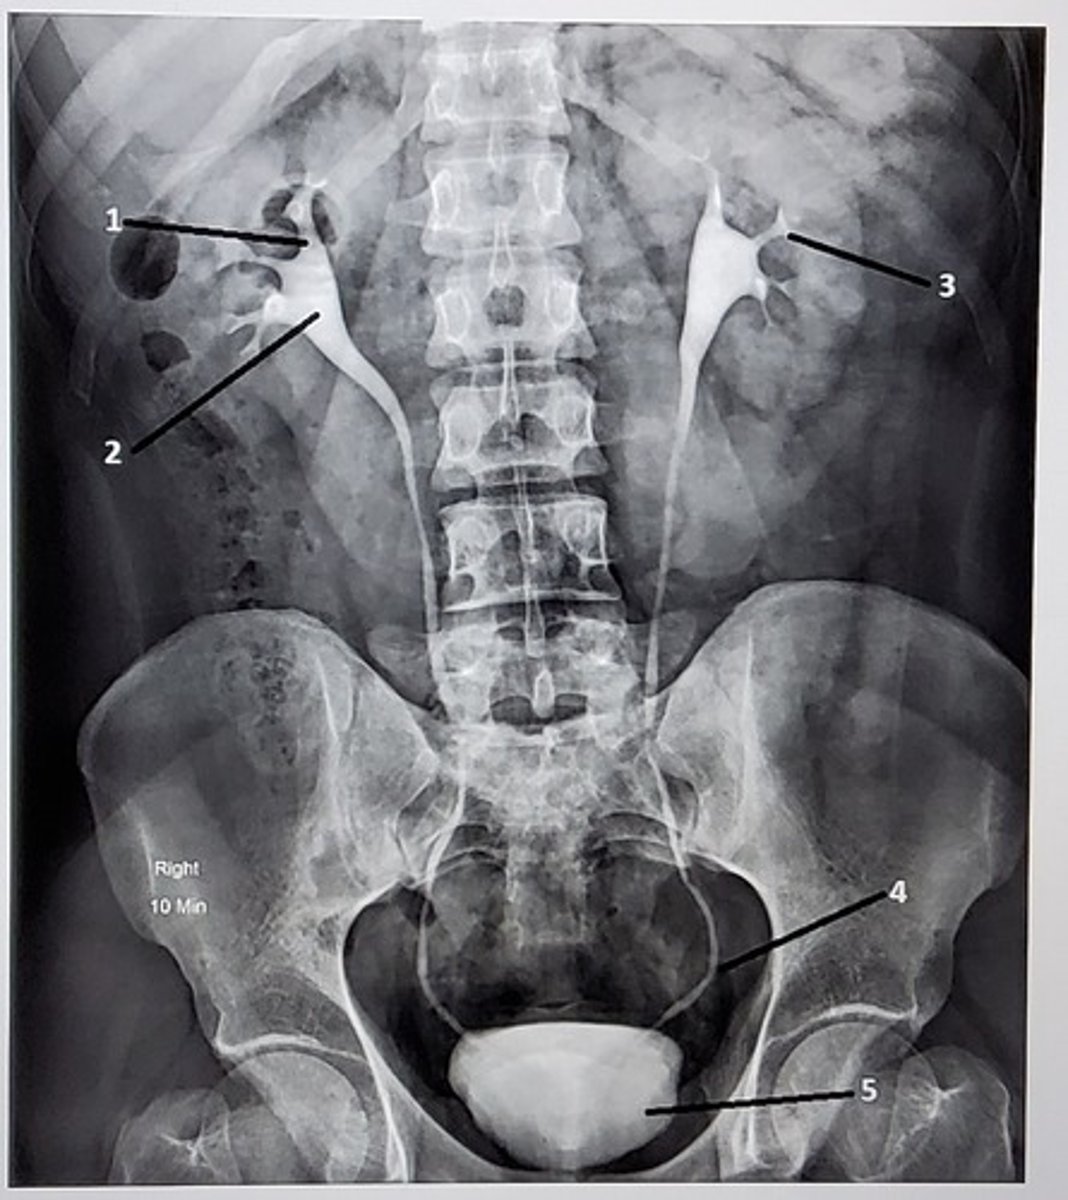

1. Right major calyx

2. Right renal pelvis

3. Left minor calyx

4. Left distal ureter

5. Bladder

Identify the anatomic structures labeled on this image. Your label should be descriptive (proximal/distal, which side of the body, etc).